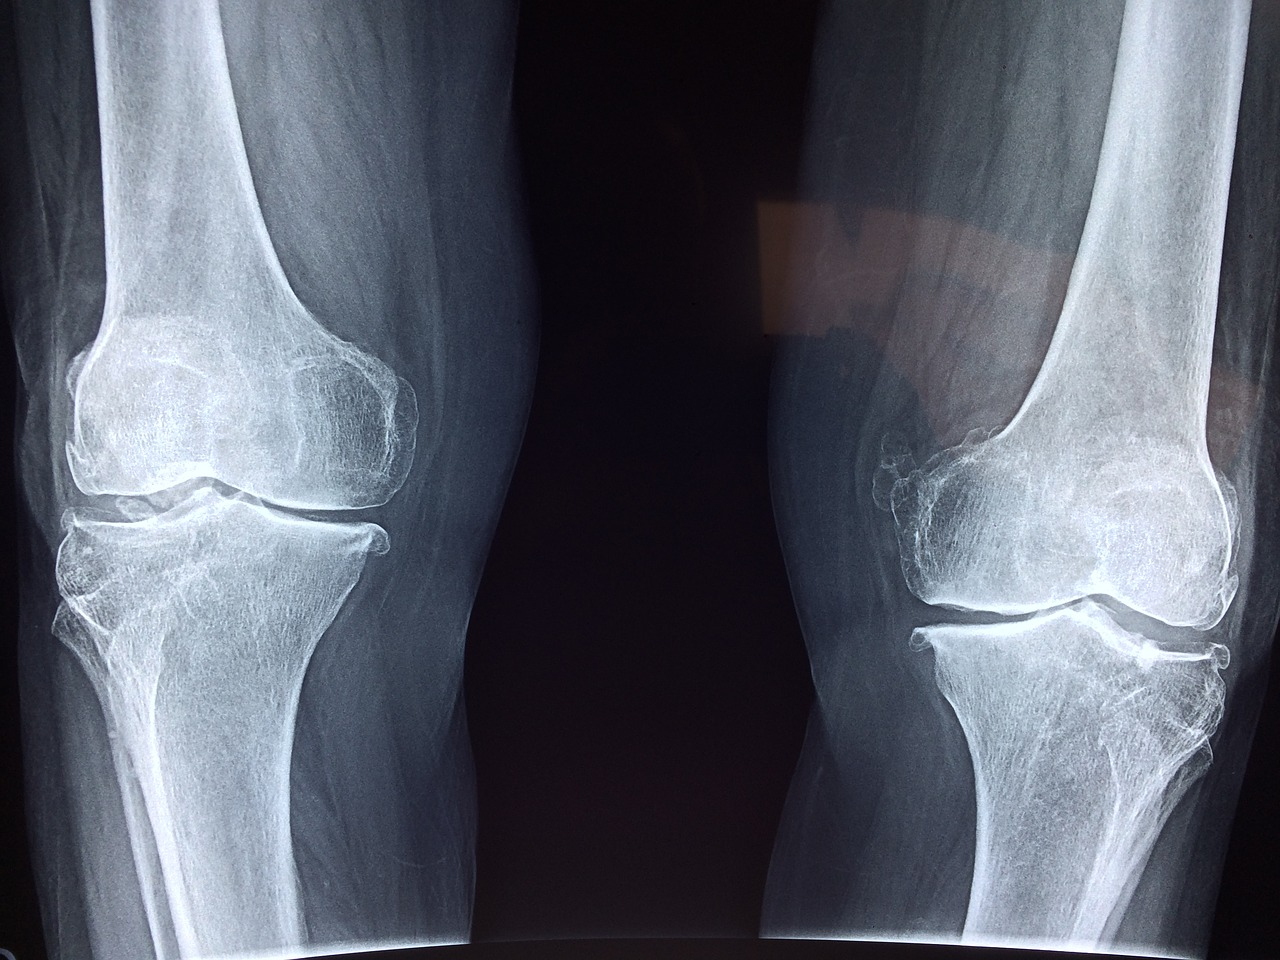

Įrodyta, kad malti kiaušinių lukštai, sumaišyti su obuolių sidro actu, yra puikus gydomasis mišinys, jei skauda sąnarius.

Kiaušinių lukštuose yra tokių medžiagų kaip kolagenas, chondroitinas, gliukozaminas ir hialurono rūgštis, kurios gerina sąnarių darbą.

Kai kiaušinio lukšto membrana ištirpsta, šios maistingosios medžiagos patenka į actą ir greitai palengvina skaudamą vietą, kai tirpalu patepate ją.